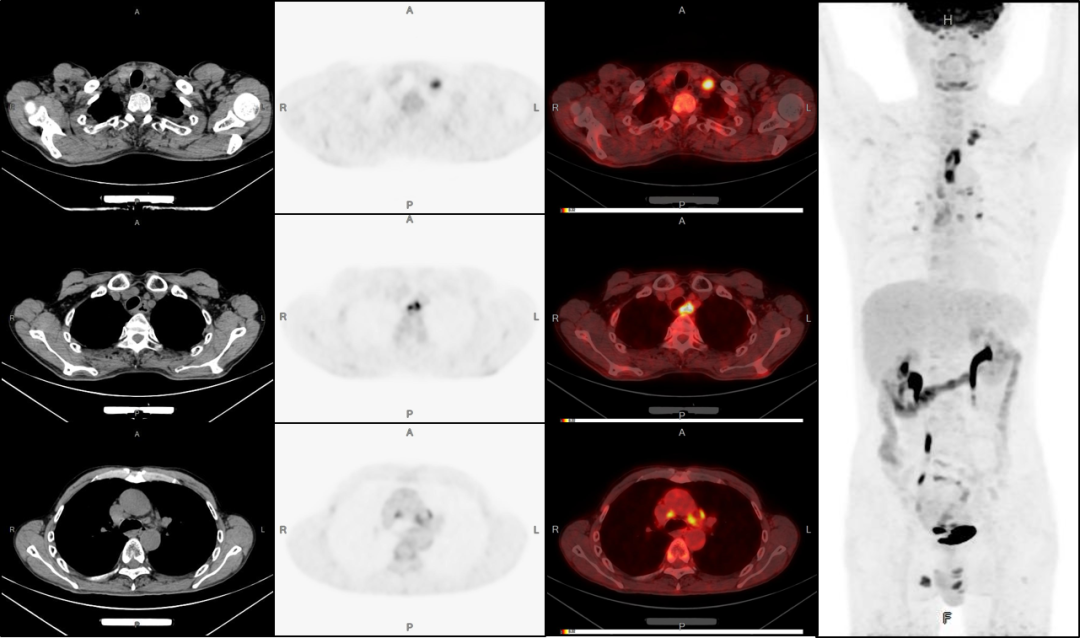

●鑒別腫瘤的良惡性,提供全身器官和組織有無腫瘤轉(zhuǎn)移的信息,對腫瘤進(jìn)行精準(zhǔn)的臨床分期;

● 腫瘤治療后的隨訪,及時指導(dǎo)臨床調(diào)整治療方案。